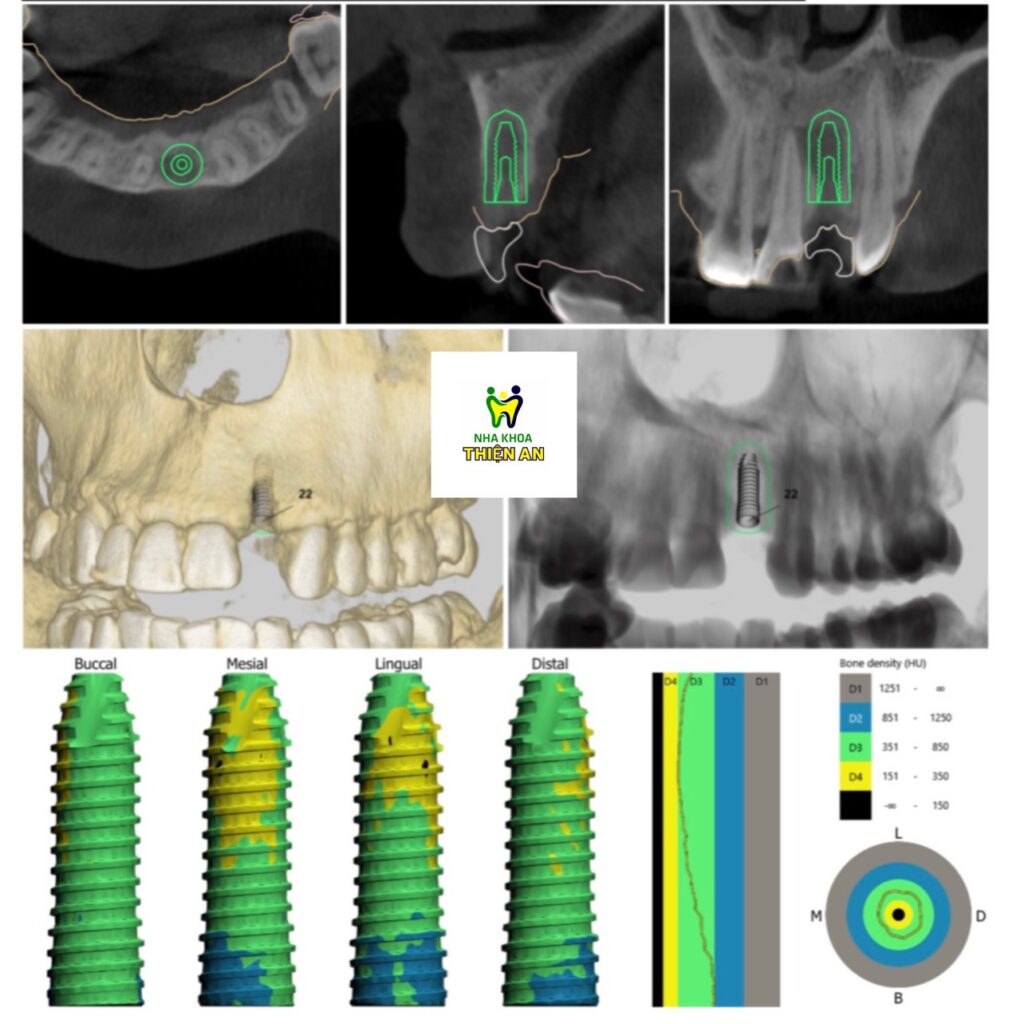

Tiếp tục là một ca cấy ghép implant vùng răng cửa bên tại nha khoa Thiện An BMT – Đăk Lăk cho anh L. (35 tuổi). Ưu điểm của phương pháp này là sẽ duy trì được chiều cao và độ dày của vùng xương ổ răng mất, ổn định theo thời gian với độ thẩm mĩ gần như răng thật mà các phương pháp khác như cầu răng sứ hoặc hàm giả tháo lắp không làm được

Next is an implant surgery in the lateral incisor area at Thien An BMT Dental Clinic – Dak Lak for Mr. L. (35 years old). The advantage of this method is that it will maintain the height and thickness of the lost alveolar bone area, stable over time with an aesthetic almost similar to real teeth that other methods such as porcelain bridges or removable dentures can’t achieve